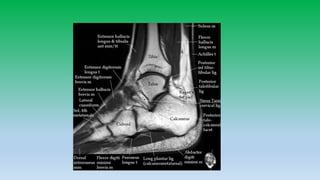

Medial aspect

Tendon: Tibialis posterior

Flexor digitorum longus

Flexor H. longus

Ligaments: Deltoid ligament